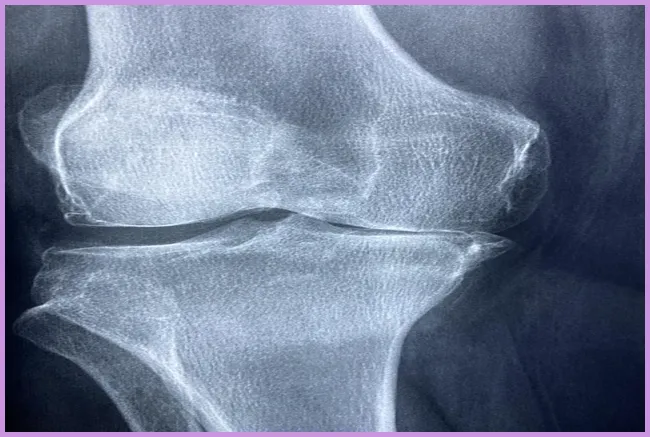

- 퇴행성 관절염: 나이가 들면서 관절의 연골이 마모되어 생기는 질환으로, 고관절 통증을 유발할 수 있습니다.

- 조직의 손상: 연골 및 주변 조직의 손상이 고관절 통증을 유발합니다.